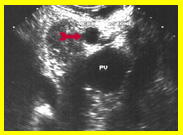

בדיקת האולטרה-סאונד היא מכשיר עזר חשוב באבחון הלוקים באבנים בכיס המרה, בצהבת או במצבים דלקתיים חריפים. אמינות הבדיקה היא גבוהה - 95%. בבדיקה זו מודגמות האבנים בכיס המרה כנקודות בהירות שמאחוריהן "צל אקוסטי" (Acoustic shadow) - אזור בלא החזרת קול (האבן חוסמת את הקול) (תצלום 1.8). אם הנבדק משנה תנוחה, האבן זזה, והדבר מודגם בבדיקה. אבנים בדרכי המרה ניתנות להדגמה ב- 20% מהמקרים. דרכי מרה מורחבות אפשר להדגים בלוקים בחסימה בדרכי המרה. בחולים אלה ההרחבה יכולה להיות של דרכי המרה החוץ ו\או התוך-כבדיות. (תצלום 2.8 ו- 3.8). נוזל סביב כיס המרה ודופן מעובה של כיס המרה מעידים על דלקת של כיס המרה (תצלום 4.8). אפשר לבצע בדיקת אולטרה-סאונד של דרכי המרה בזמן הניתוח ולאתר אבנים בדרכי המרה.